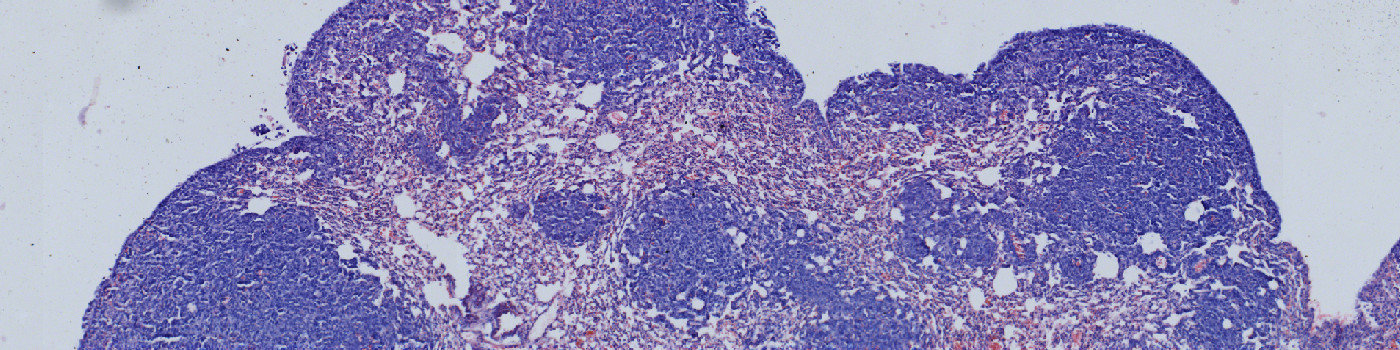

This protocol can be used to quantify metastases in H&E stained lung sections. The APP detects the total area of the lung tissue, delineates and separates the metastases and quantifies the area for each metastatic nodule. In the end, the total tissue area, the number of metastases, the area of each metastasis and the metastatic area percentage are given.

Step 2: Load the APP for metastases detection “02 Metastasis Detect” which identifies the metastases inside the lung tissue.

The first image processing step involves a segmentation of the lung tissue (see FIGURE 1). Afterwards the metastases are identified together with the regions that are either too misshaped, too red or too sparse for being identified as metastases (see FIGURE 5). The parameters defining the shape and sparseness of the metastases can easily be adjusted by the user.